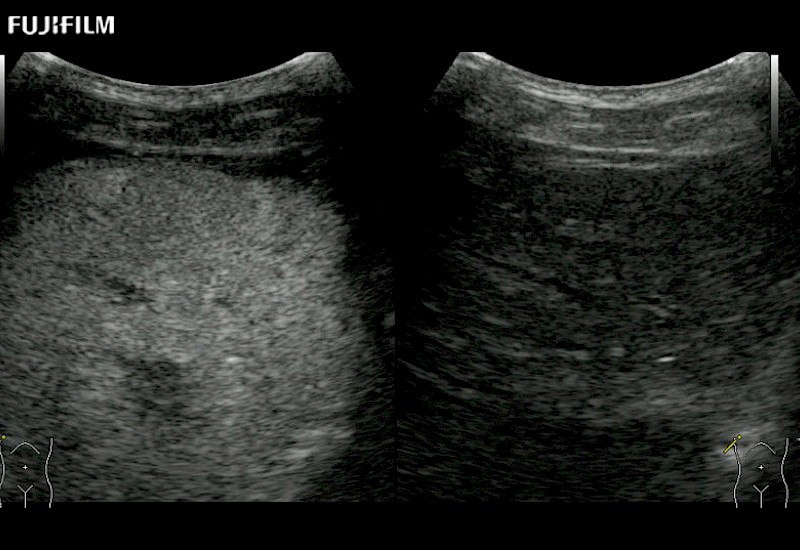

Extraordinary high-resolution digital imaging

- Exceptional near and far-field resolution

- Instant feedback on tumor margin delineation

- Valuable information to guide tumor resections

- Exceptional near and far-field resolution

- Instant feedback on tumor margin delineation

- Exceptional near and far-field resolution

- Exceptional near and far-field resolution

- Instant feedback on tumor margin delineation

- Exceptional near and far-field resolution

- Instant feedback on tumor margin delineation

- Exceptional near and far-field resolution

- Instant feedback on tumor margin delineation

- Exceptional near and far-field resolution

- Instant feedback on tumor margin delineation

- Valuable information to guide tumor resections

- Exceptional near and far-field resolution

- Instant feedback on tumor margin delineation

- Valuable information to guide tumor resections

- Exceptional near and far field resolution

- Instant feedback on tumor margin delineation

- Valuable information to guide tumor resections

- Exceptional near and far-field resolution

- Instant feedback on tumor margin delineation

- Valuable information to guide tumor resections

- Exceptional near and far field resolution

- Instant feedback on tumor margin delineation